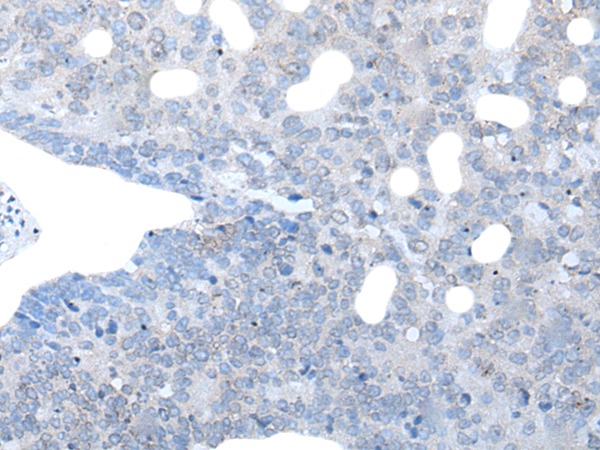

分类: 科研抗体货号: P05886别名: IL6Q; gp80; CD126; IL6RA; IL6RQ; IL-6RA; IL-6R-1应用: IHC反应种属: Human